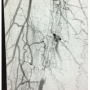

A 46-year-old female presented with a non-healing wound on the right foot. Duplex ultrasound suggested an occluded distal right superficial femoral artery (SFA). Single leg right lower extremity arteriogram runoff revealed the 100% occlusion in the distal right SFA before Hunter’s canal (Figure 1), mild atherosclerotic disease in the right profunda femoris, and 3-vessel runoff to the right foot. The occluded segment appeared to be moderately calcified proximally and the plaque heterogeneous in nature.